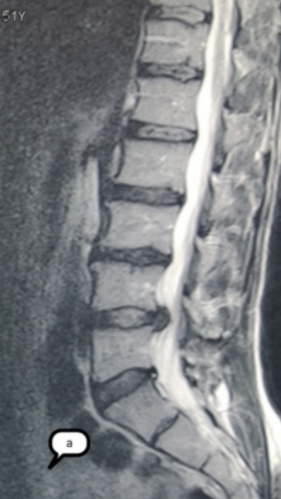

Грыжа Диска L4-L5

3 процедуры ФДТ, 9 процедур MBST

Параметры изменяются в зависимости от процедуры

Дата публикации: 22.08.2025 14:27:20